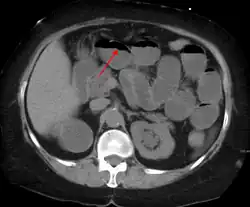

Radiological signs of bowel obstruction include bowel distension (small bowel loops dilated >3 cm) and the presence of multiple (more than 2) air-fluid levels on supine and erect abdominal radiographs.[16] Ultrasounds may be as useful as CT scanning to make the diagnosis.[17]

Contrast enema or small bowel series or CT scan can be used to define the level of obstruction, whether the obstruction is partial or complete, and to help define the cause of the obstruction. The appearance of water-soluble contrast in the cecum on an abdominal radiograph within 24 hours of it being given by mouth predicts resolution of an adhesive small bowel obstruction with sensitivity of 97% and specificity of 96%.[18]